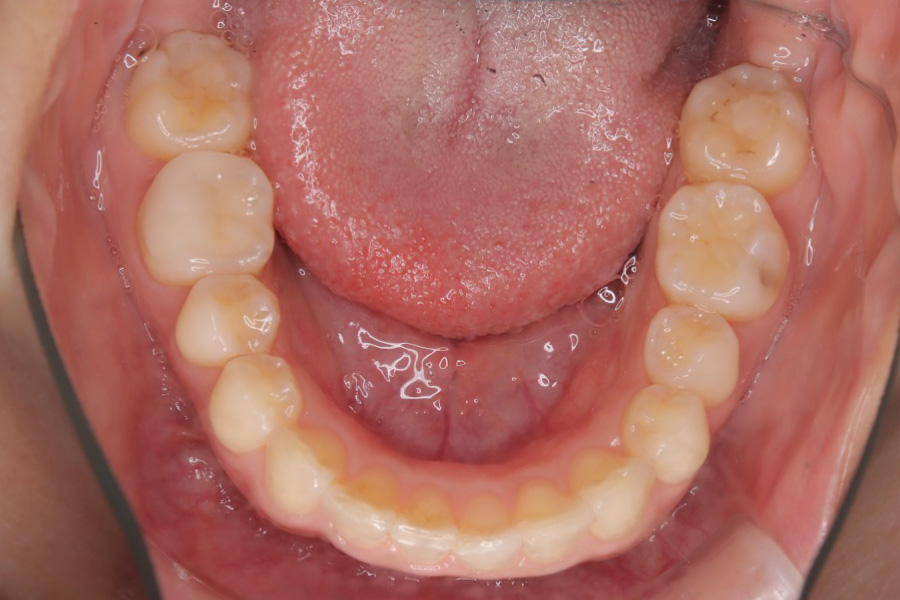

【20代女性】

全体のガタつきを

インビザライン矯正で治療したケース

治療後

主訴 全体のガタつきが気になる

治療内容 インビザライン矯正

非抜歯